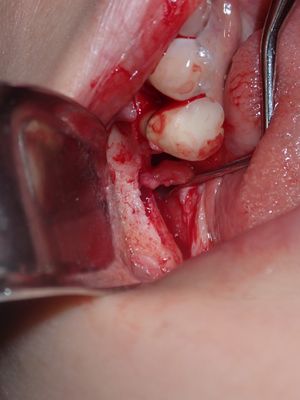

TZeng - vertical bone graft

large crestal defect from previous perio infection, site prepared with small little osteotomies and grafted with sticky bone from allograft/20% xeno, collagen membrane soaked in prf fluid tacked with three membrane tacks, additional fibrin membrane placed.